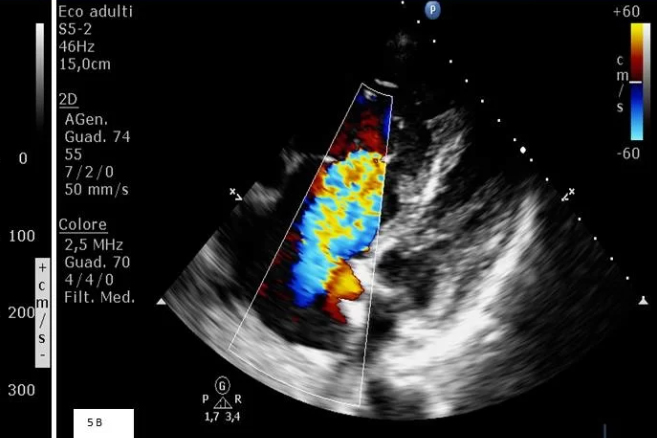

È un’infiammazione dell’endocardio, il rivestimento interno delle cavità e delle valvole cardiache, causata da microorganismi patogeni che si insinuano nel sangue fino a raggiungere il cuore. Possono provenire da altre parti del corpo (bocca, intestino, apparato urinario, pelle) o essere trasmessi attraverso procedure mediche invasive di varia natura.

Se un paziente presenta problematiche cardiache pregresse e magari un deficit immunitario, il cuore è più facilmente esposto all’aggressione dei microrganismi che trovano le condizioni ideali per annidarsi, in genere sulle valvole cardiache, formando degli accumuli chiamati vegetazioni.

Le temibili complicanze potrebbero essere stenosi e rigurgito valvolare, embolia ed ictus, scompenso cardiaco e setticemia.